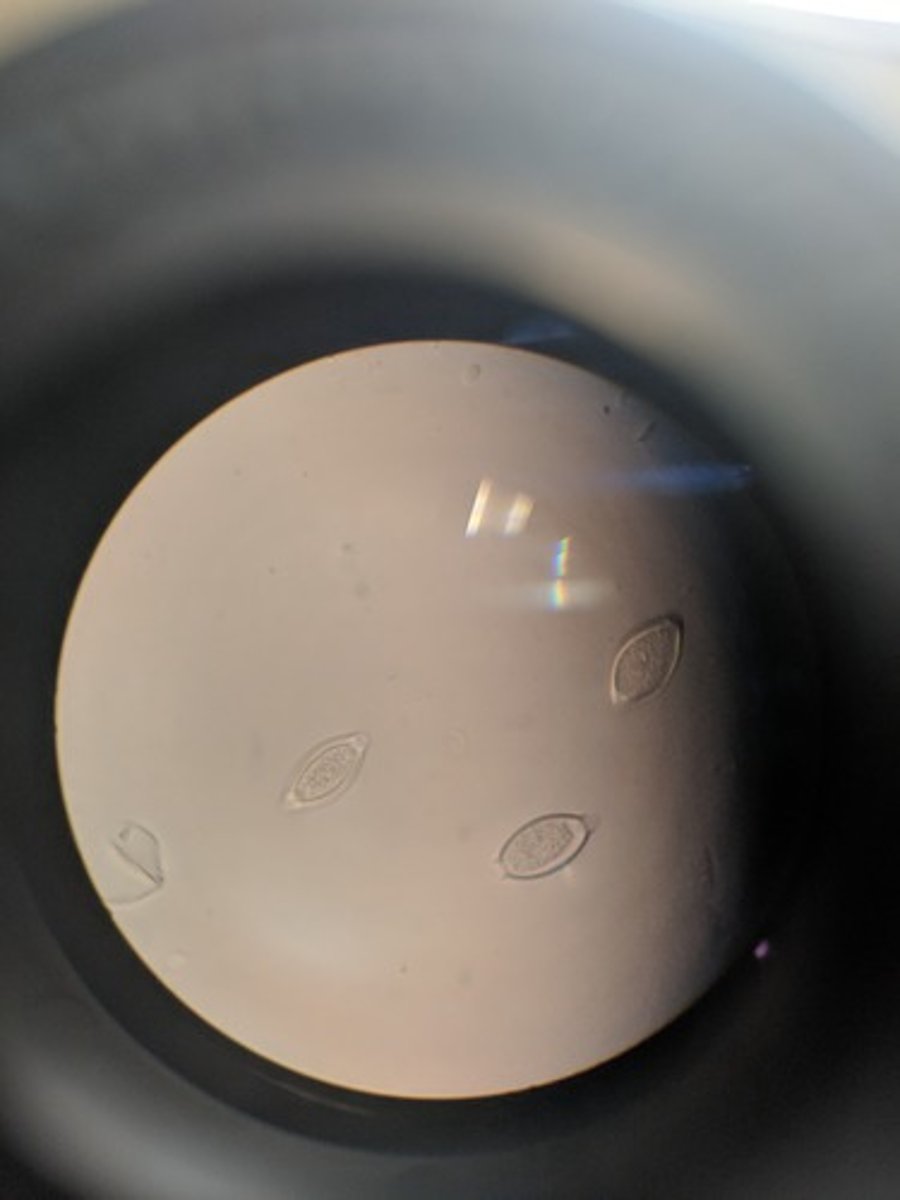

Enterobius vermicularis (roundworm)

- pinworm

- very abundant like grains of rice

- egg shape with one flat side

- larvae worm folded in half

-transparent shell

Eggs = infective form

dx: fecal exam for eggs / scotchtape method